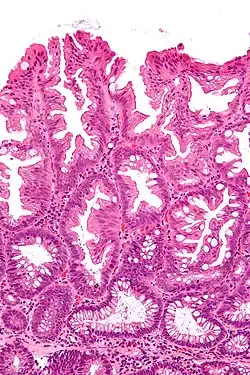

| Micrograph of a sessile serrated lesion. H&E stain. | |

SSLs are diagnosed by their microscopic appearance; histomorphologically, they are characterized by (1) basal dilation of the crypts, (2) basal crypt serration, (3) crypts that run horizontal to the basement membrane (horizontal crypts), and (4) crypt branching. The most common of these features is basal dilation of the crypts.

Unlike conventional colonic adenomas (e.g. tubular adenoma, villous adenoma), they do not (typically) have nuclear changes (nuclear hyperchromatism, nuclear crowding, elliptical/cigar-shaped nuclei).